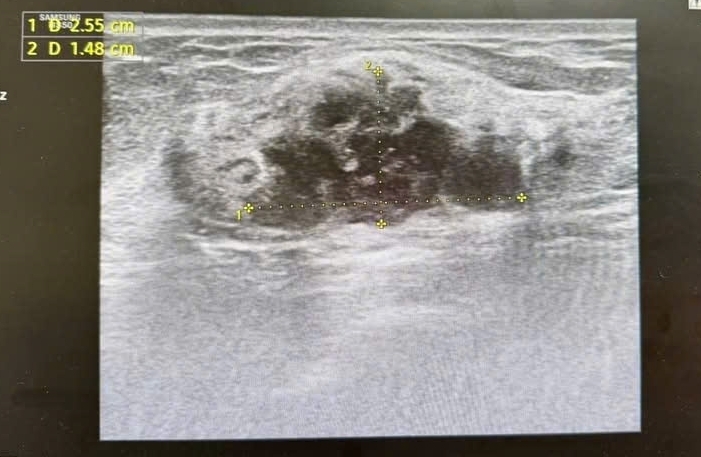

Hình ảnh khối u được phân loại BIRADS 4 trên siêu âm và chụp X-quang tuyến vú.

Các xét nghiệm tiếp theo, bao gồm chọc hút tế bào, xác định người bệnh mắc ung thư biểu mô tuyến vú giai đoạn sớm.